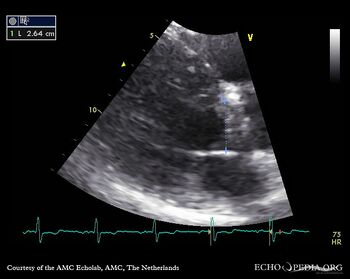

Aortic valve stenosis

AoS13